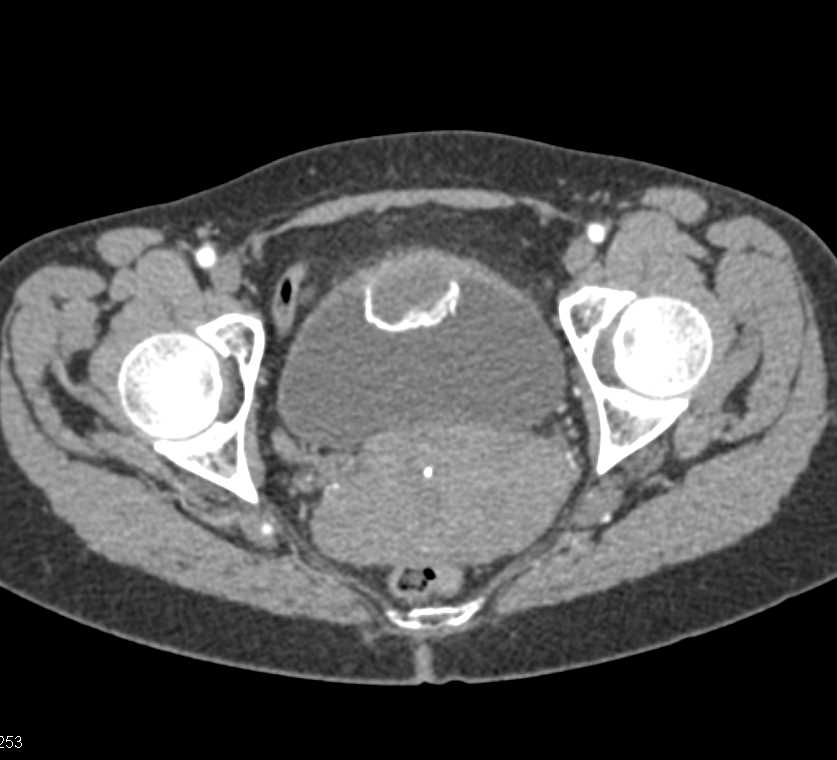

Urachal Carcinoma of the Bladder